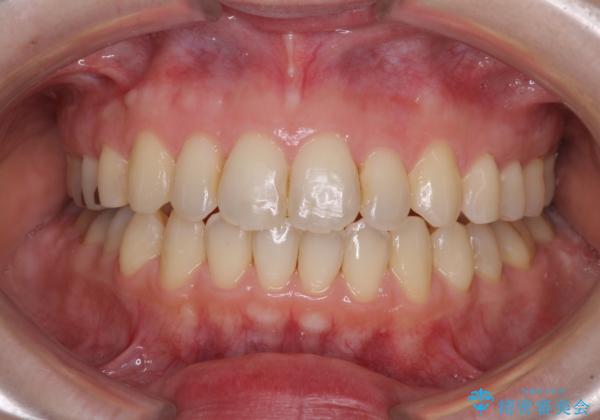

- 前歯のデコボコを気にして来院された患者様です。

下顎が骨格的にずれており、上下正中を合わせることは難しいことが予想されたため、デコボコの解消を主目的として、ワイヤー矯正を行うこととしました。

治療途中で出産されたこともあり、当初予定よりも終了までに期間がかかってしまいました。

舌を前方に突出する癖があったため、上下前歯がなかなか接触しなかったことも治療期間が伸びた要因です。